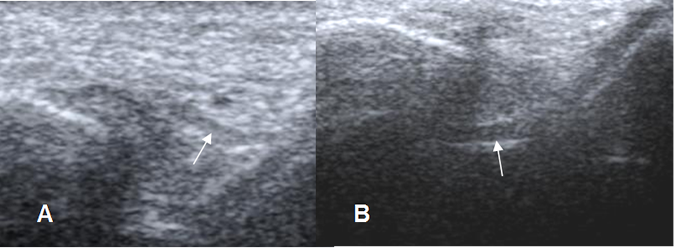

En ecografía, los ligamentos son estructuras lineales e hipoecoicas, con un espesor menor a 2 mm. (4). (Fig 9 y 15).

Fig 9. Ligamentos peroneoastragalinos normales en ecografía.

Ligamento peroneoastragalino anterior en A y peroneoastragalino posterior en B.